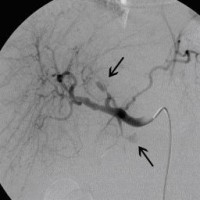

Postoperative abdominelle Blutungen bei chronischer Pankreatitis (Pfeile: Art. hepatica und Art. gastroduodenalis).

(Bild 1 von 5)